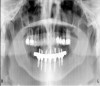

Figure 11a  Insufficient crown height space for bar overdenture because of the vertical dimension of the mandible.

Figure 11a

Figure 11b  Osteoplasty performed at the time of implant placement to gain sufficient crown height space.

Figure 11b